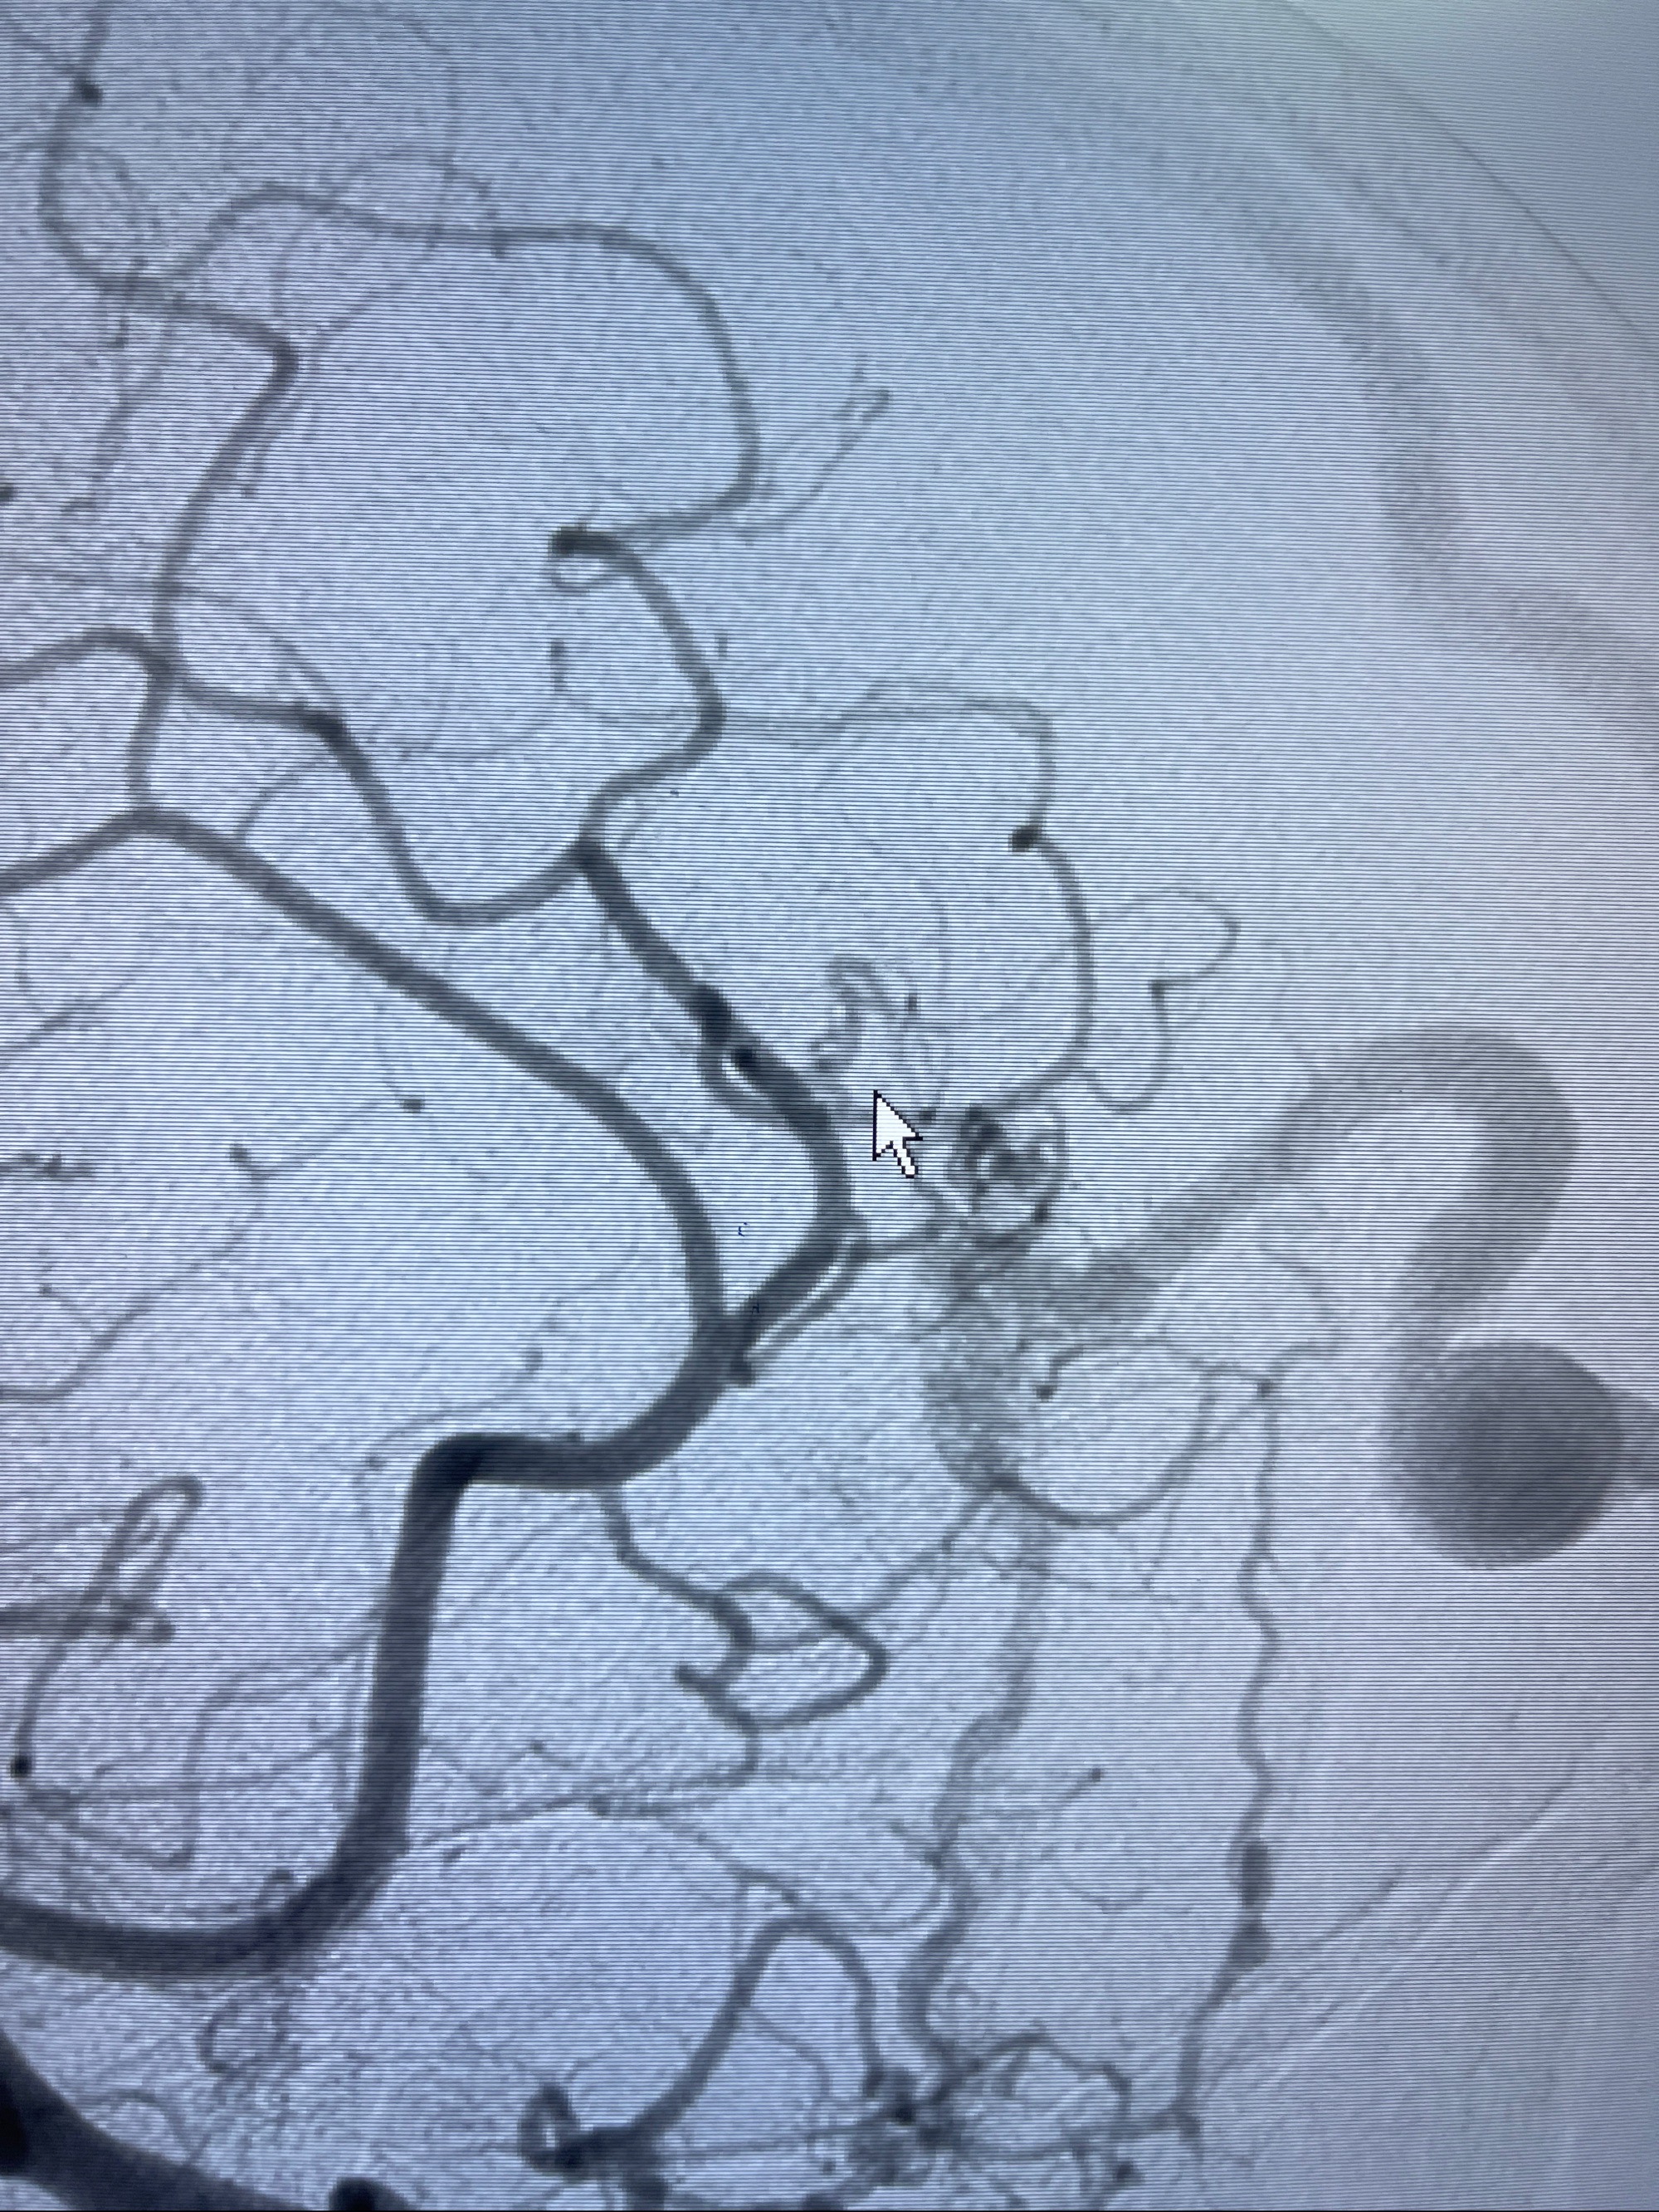

2023年8月21日]景德镇市第一人民医院脑血管造影检查,提示:主动脉弓、双侧颈总动脉、锁骨下动脉造影未见异常,左侧大脑前动脉静脉瘘。

2023-09-13全脑血管造影:前颅底硬脑膜动静脉瘘,供血动脉为双侧胼周动脉、眼动脉脑膜支,静脉向上矢状窦方向引流

- 介入干预:静脉途径栓塞or动脉途径填塞?